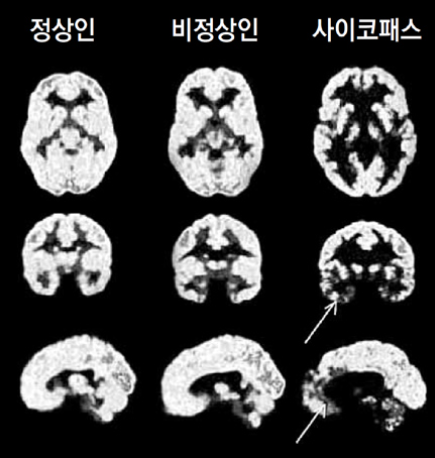

전문가들은 김 씨의 범행 수법과 이후 행보를 볼 때, 그녀가 전형적인 사이코패스 혹은 통제형 살인마일 가능성에 무게를 두고 심층 분석을 이어가고 있습니다. 범행 후 피해자에게 태연하게 문자를 보내거나 SNS에 본인의 셀카를 올리며 새로운 만남을 시도하는 모습은 극도의 공감 능력 결여를 보여주는 대목입니다.

일부 프로파일러들은 그녀가 자신의 통제하에 타인의 생명이 좌우되는 상황에서 **심리적 우월감과 쾌락을 느끼는 '통제형 범죄'**의 특성을 보인다고 지적했습니다. 특히 증거가 제시되어도 일관되게 거짓 답변을 되풀이하는 모습은 죄책감을 전혀 느끼지 않는 사이코패스적 성향과 일치한다는 의견이 지배적입니다. 현재 진행 중인 사이코패스 진단 검사(PCL-R) 결과에 따라 그녀의 범행 동기가 더욱 구체화될 것으로 보이나, 대중을 향한 공격성과 과시욕은 이미 위험 수위를 넘었다는 평가입니다.